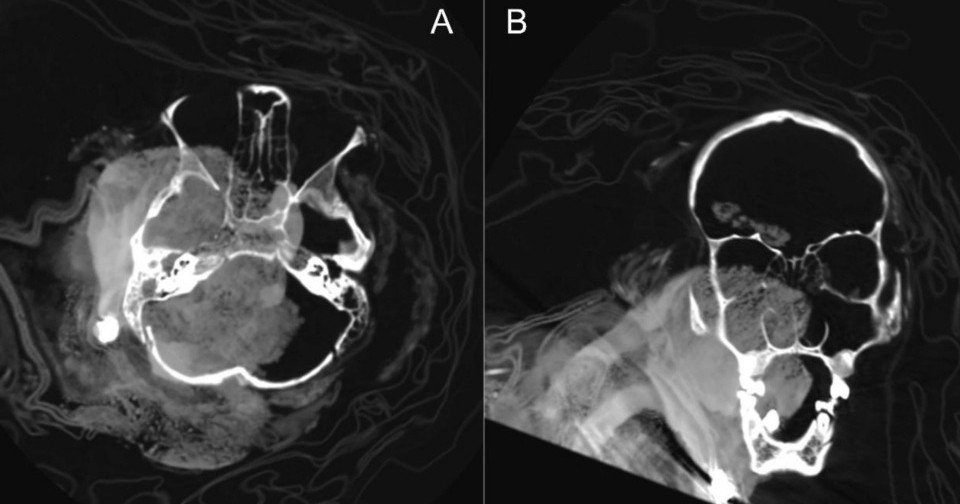

Исследователи решили проанализировать с помощью компьютерной томографии останки четырех человек (всех упомянутых, кроме мальчика Ampato-3, чье захоронение пострадало от молнии). Они определили, что мумии с вершин Ампато и Сара-Сара принадлежали девочкам примерно одного возраста — около 14 ± 2 года. Два изученных ребенка, останки которых покоились ниже по склону Ампато, были младше. По оценкам специалистов, на момент смерти им было 8 ± 2 (Ampato-2) и 10 ± 2 (Ampato-4) года.

Анализ костей этих детей показал, что обе девушки с вершин вулканов перед смертью, по-видимому, получили серьезные черепно-мозговые травмы, которые вполне могли быть фатальными. Вполне возможно, что прижизненные травмы получили и девочки Ampato-4 и Ampato-2. Однако ученые подчеркнули, что на компьютерных томограммах сложнее отличить переломы костей, полученные при жизни и после смерти, чем в случаях, когда ученые работают не с мумифицированными останками и используют различные микроскопические методы. Кроме того, у ребенка Ampato-2 исследователи выявили патологию пищевода и кальцинаты в легких, которые противоречат мнению о том, что для капакочи отбирали детей с идеальным здоровьем.

Отдельный интерес представляет мумия Ampato-4. Исследование этих останков показало, что спустя какое-то время после смерти люди проводили манипуляции с телом ребенка. Ученые обнаружили, что многие кости внутри мумии были смещены, а некоторые и вовсе отсутствовали. Кроме того, внутри грудной клетки они заметили инородные предметы, представляющие собой камни и куски ткани. Вполне вероятно, что люди привели в надлежащий вид замороженную мумию через какое-то время после смерти ребенка (возможно, она произошла не в том месте, где впоследствии исследователи нашли останки), так как сохранность тела ребенка была важным атрибутом ритуала.